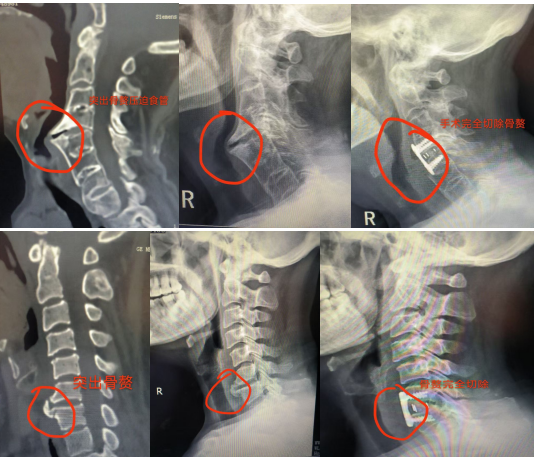

针对患者复杂的病情,骨伤科专家团队经过深入研讨和精心准备,为他们制定了个性化的手术方案,采用了颈椎前路减压植骨融合术(ACDF)这一先进的手术方法。手术当天,在经验丰富的主刀医生带领下,手术团队成员各司其职,配合默契。他们在高清显微镜的辅助下,小心翼翼地避开颈部复杂的血管和神经,精准地对病变的颈椎部位进行减压操作,去除了压迫食管的增生组织和椎间盘,随后植入精心挑选的骨移植材料,以促进颈椎的融合和稳定。整个手术过程如同一场精密的 “手术交响乐”,每个环节都紧密相连,有条不紊地进行着,充分展现了骨伤科团队精湛的医术。

值得一提的是,在整个诊断和手术过程中,医院高分辨率的 MRI 和 CT 扫描技术等高端设备如同医生的 “透视眼”,清晰地呈现出颈椎和食管的细微结构,为准确诊断病情和制定手术方案提供了坚实的依据,大大提高了手术的精准性和安全性,让医生们如虎添翼。